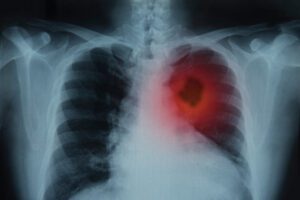

To tell the story now, he says I was a runaway freight train. My lungs looked like a shotgun blast went off inside. I had cancer in my lymphatic system that had spread to the bones and affected the blood. We began an onslaught of testing for the cancer and stroke prevention. I had three more blood clots and blood pooling behind my heart. He wouldn’t tell me this then, but he thought I only had three months to live.